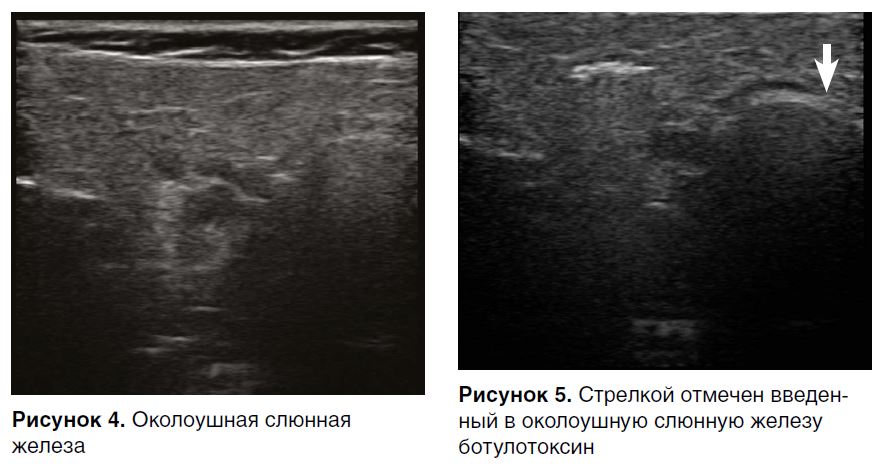

Препарат вводится непосредственно в околоушные и подчелюстные слюнные железы (рис. 3) под контролем ультразвука (до введения — рис. 4, после — рис. 5).